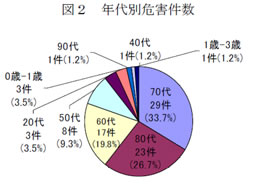

解答 解説 ある物 を誤飲したとして来院した80歳代女性 実践 画像

解答 解説 ある物 を誤飲したとして来院した80歳代女性 実践 画像

解答 解説 ある物 を誤飲したとして来院した80歳代女性 実践 画像

解答 解説 ある物 を誤飲したとして来院した80歳代女性 実践 画像

高齢者の誤飲 誤食が増加中 最も危ないのは薬の包装シート 不慮の

高齢者の誤飲食で最も多い 薬の包装の誤飲 に注意しましょう Rme

高齢者の誤飲 誤食が増加中 最も危ないのは薬の包装シート 不慮の

高齢者の誤飲事故 内服薬の包装が4割を占める コラム De スタディ

高齢者の誤飲 誤食が増加中 最も危ないのは薬の包装シート 不慮の

高齢者の誤飲 誤食が増加中 最も危ないのは薬の包装シート 不慮の